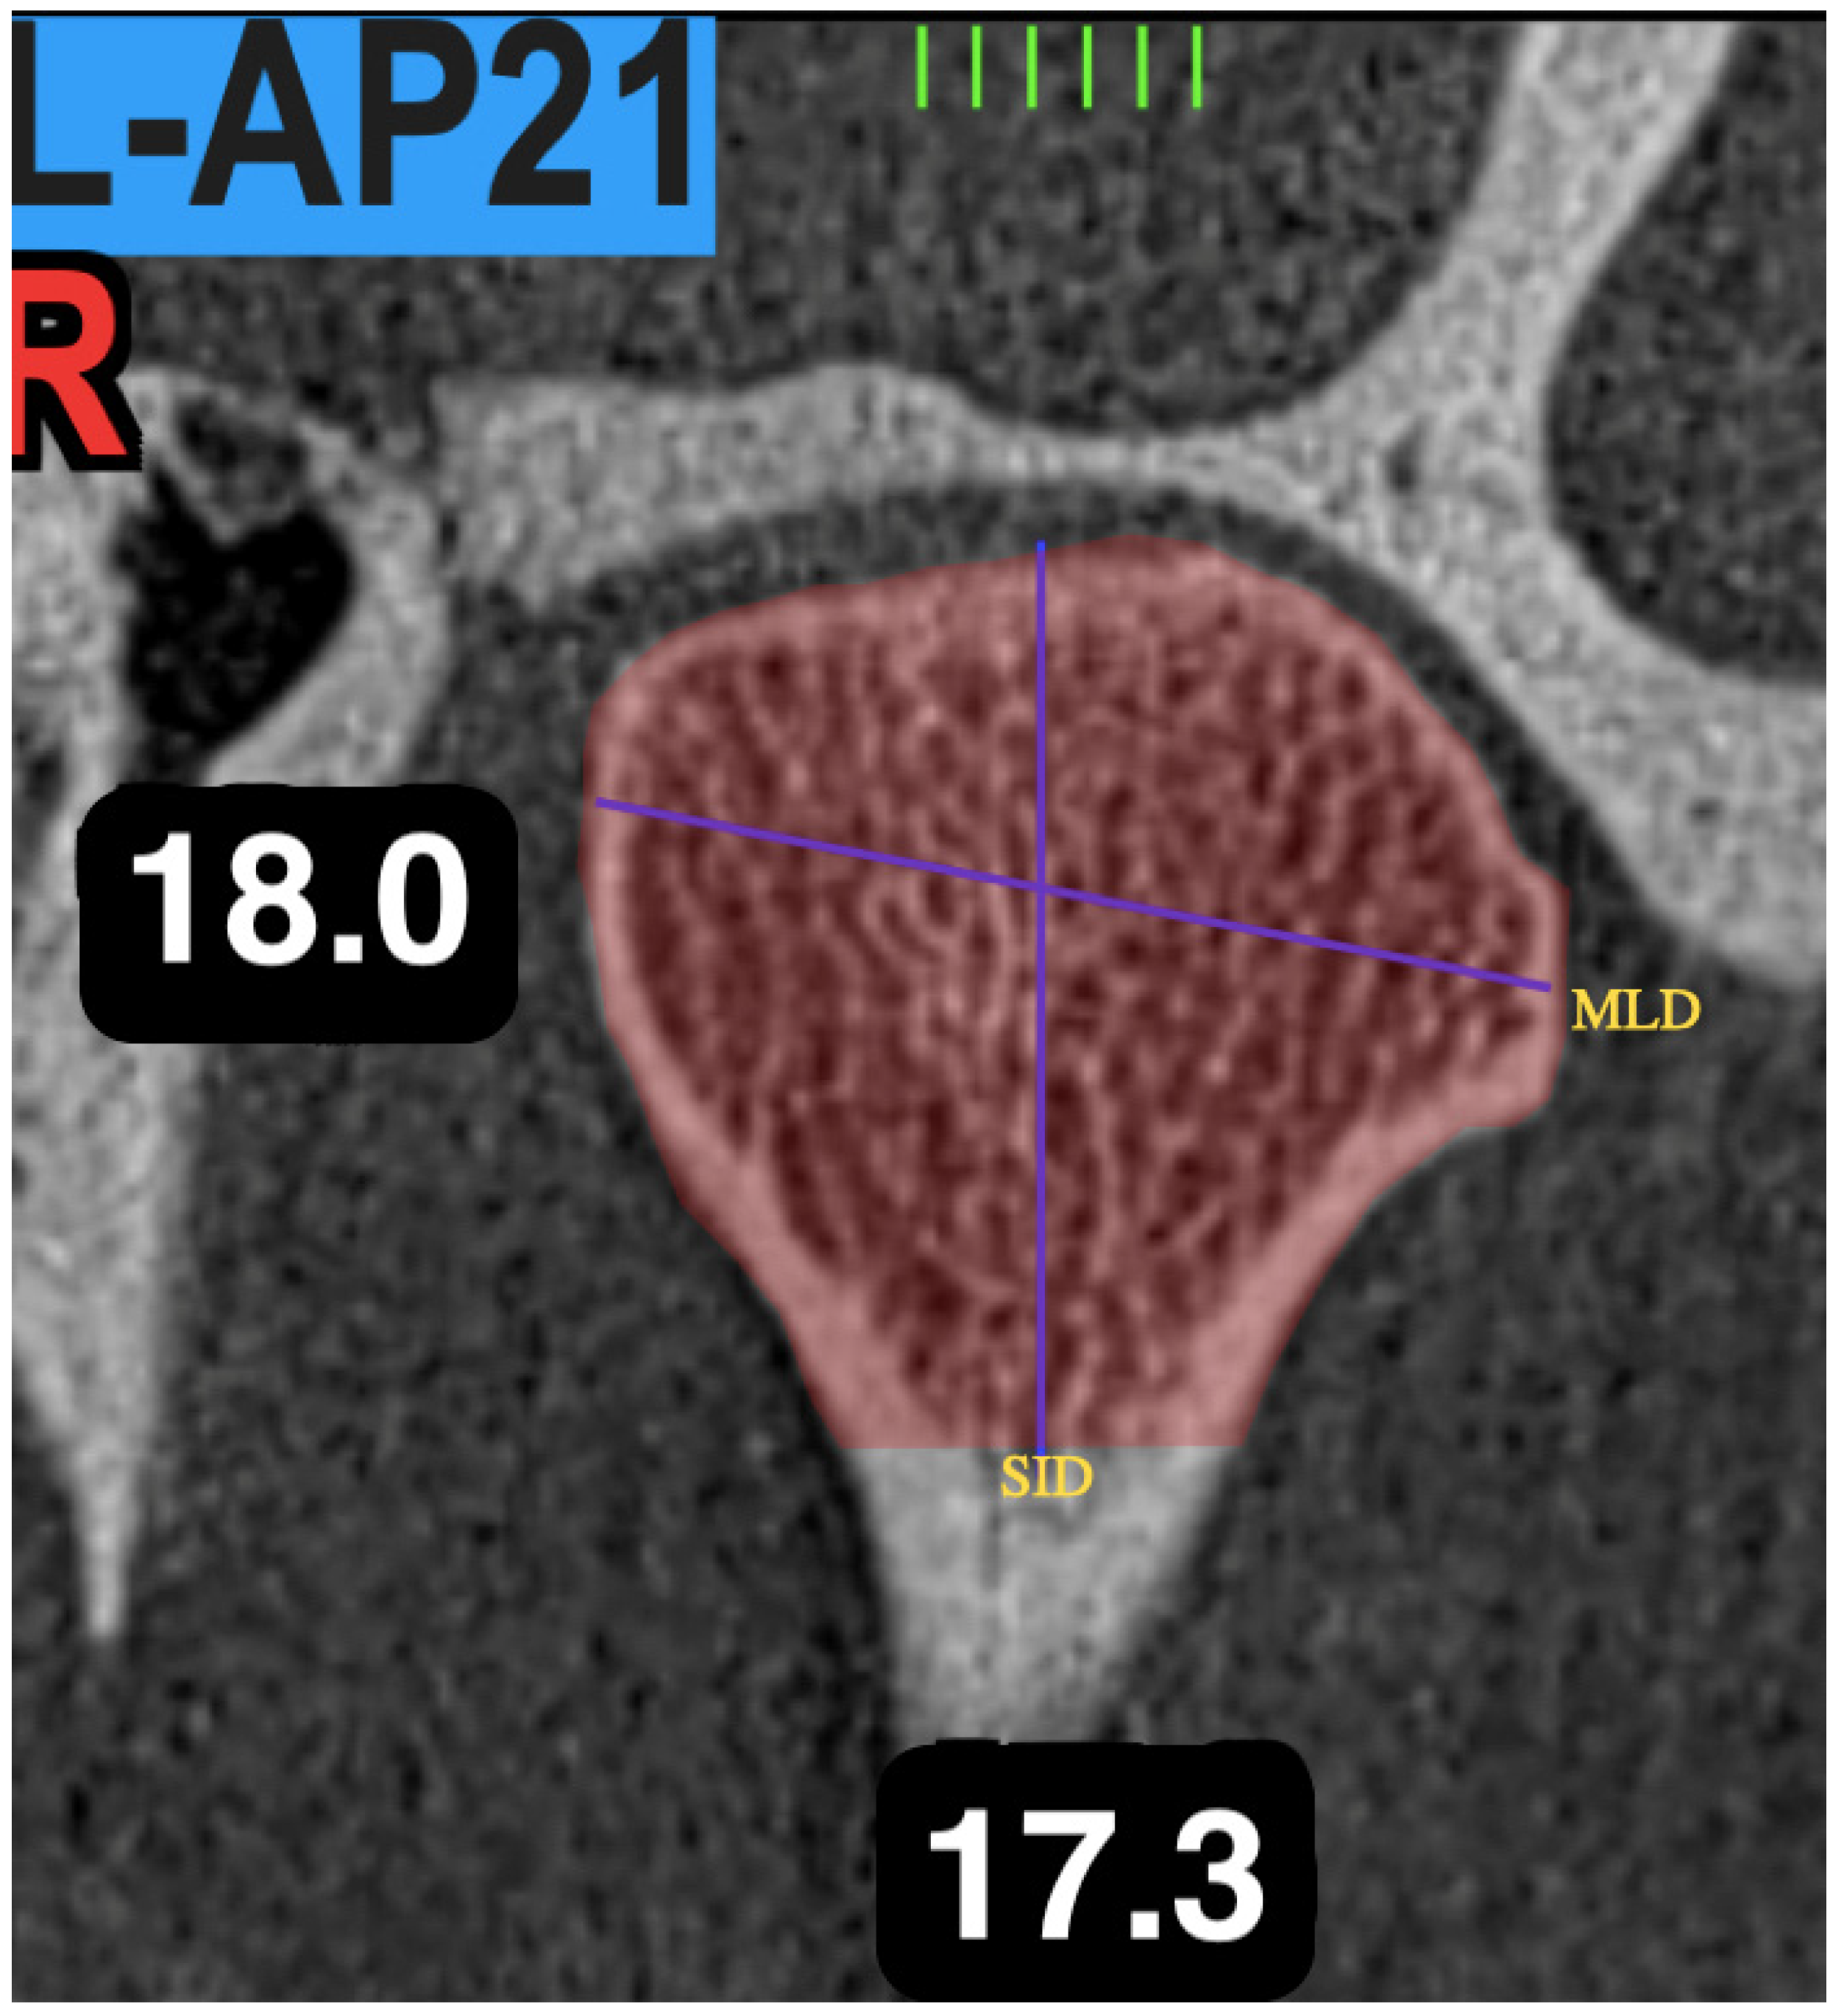

2.5. Coronal Analysis of the Condyle

| Mediolateral Distance of the Condyle | Distance between the most medial and most lateral cortical point of the condyle. |

| Vertical Distance of the Condyle | Distance between the highest cortical point and the lowest point of the condylar head |

| MLD | 21.90 mm | 4.67 | 22.07 mm | 4.75 | 19.99 mm | 3.40 | 19.82 mm | 3.74 | 0.009 * |

| VD | 19.37 mm | 4.49 | 20.12 mm | 4.23 | 18.52 mm | 4.22 | 18.57 mm | 4.01 | 0.47 |

| MLD | 19.43 mm | 3.90 | 19.66 mm | 4.41 | 23.03 mm | 3.24 | 22.55 mm | 3.48 | 0.0001 * |

| VD | 17.07 mm | 4.05 | 17.98 mm | 4.19 | 21.91 mm | 2.86 | 21.27 mm | 3.16 | 0.0001 * |